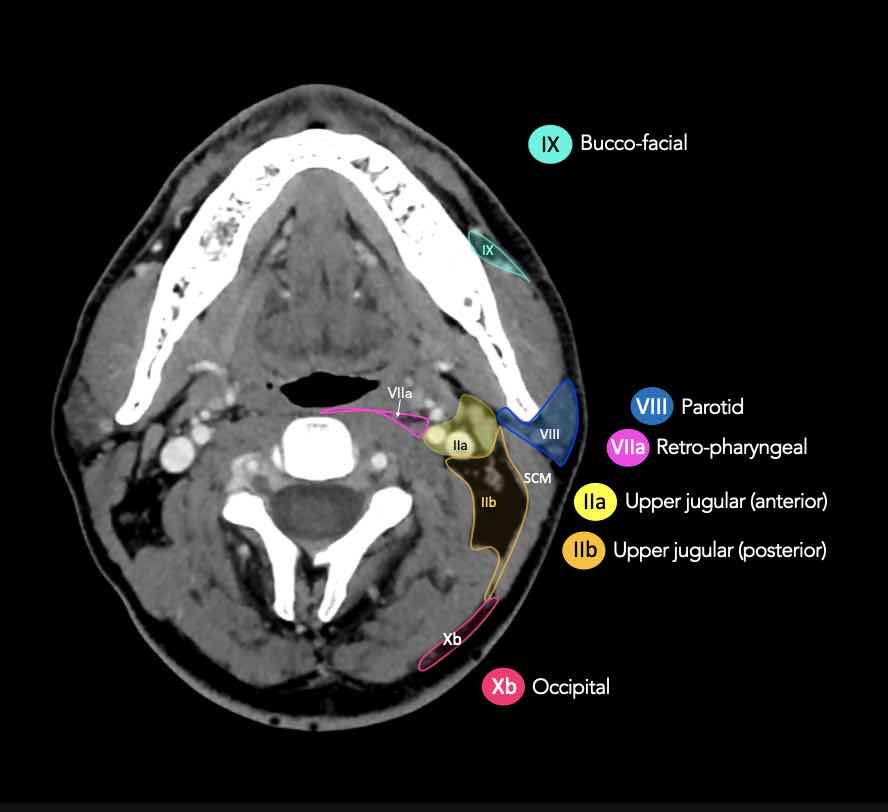

CT Scan Mặt Cắt Ngang (Axial CT)

Các lát cắt CT mặt phẳng ngang tương ứng với hình minh họa tổng quan.

Các lát cắt CT mặt phẳng ngang với hình ảnh chi tiết hơn.

Nhấp vào hình ảnh để phóng to.

II – Tĩnh mạch cảnh trên

Tầng II nhận bạch huyết hướng tâm từ mặt, tuyến mang tai, và các hạch dưới hàm, dưới cằm và sau hầu.

Tầng II cũng nhận trực tiếp các bạch mạch thu thập từ hốc mũi, hầu, thanh quản, ống tai ngoài, tai giữa, và các tuyến dưới lưỡi và dưới hàm [1].

Tầng II có thể được chia thành tầng IIa và tầng IIb bằng cách vẽ một đường tại bờ sau của tĩnh mạch cảnh trong.

Các hạch bạch huyết ở tầng IIa và IIb có nguy cơ chứa di căn từ các ung thư hốc mũi và khoang miệng, vòm hầu, hầu miệng, hạ hầu, thanh quản và các tuyến nước bọt lớn.

Tầng IIb thường liên quan hơn đến các khối u nguyên phát ở hầu miệng hoặc vòm hầu, và ít thường xuyên hơn với các khối u ở khoang miệng, thanh quản hoặc hạ hầu [1].